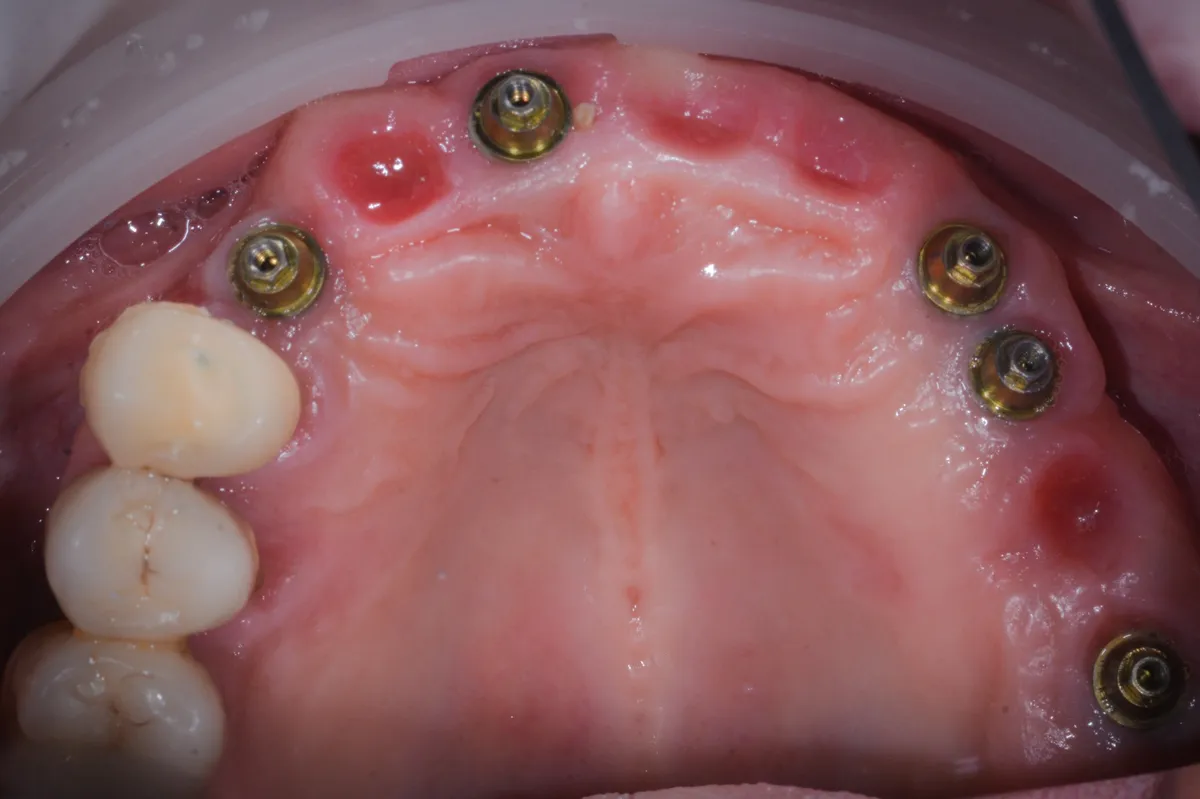

Caso clinico: espansione crestale ERE con impianto immediato e rigenerazione simultanea. Da ponte fallito a impianto in un'unica seduta.

Caso clinico LMSF graftless: due impianti a 1.6/1.5 con espansori a vite calibrati. Gestione localizzata del seno mascellare, senza innesto.

Caso clinico di peri-implantite severa trattata con decontaminazione TST (Ten Second Technique) e rigenerazione ossea guidata. Follow-up a 2 anni.

Caso clinico di carico immediato su rialzo crestale del seno mascellare con espansori. Espansione apicale, stabilità >50 Ncm, provvisorio immediato e co...